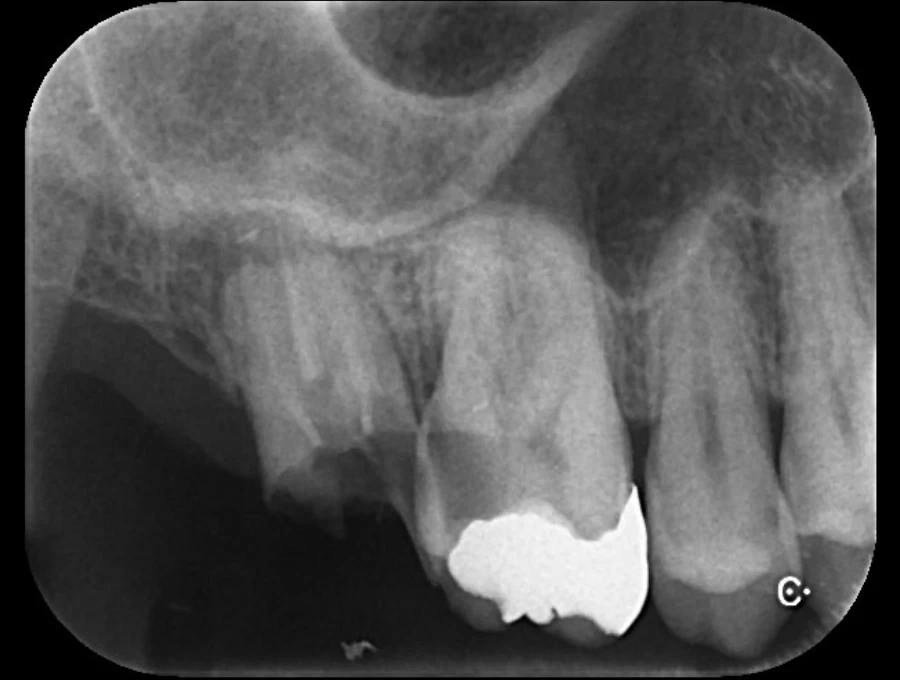

精密検査

実際にお口の中の状態をチェックしていきます。レントゲン撮影にて歯や骨の検査を行い、虫歯や治療痕のチェック、歯周病検査などの各種検査を行い、総合的な診断を下します。